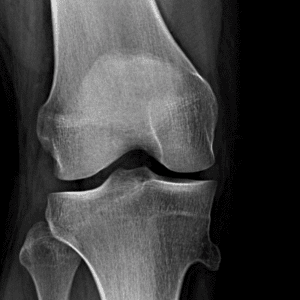

Pediatric Radiographs